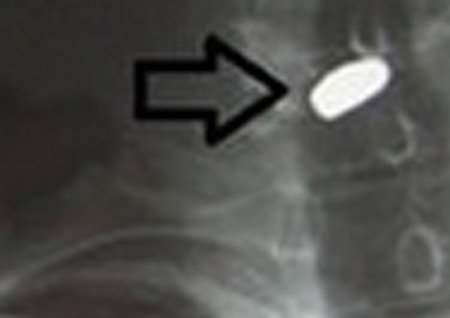

Đêm 22/1, ông Toàn vào cấp cứu tại Bệnh viện Việt Đức trong tình trạng có vết đạn bắn xuyên cổ. Phim X-quang cho thấy viên đạn dính vào tủy sống. Theo lời ông, trên đường đi đổ xăng, ông bỗng nhặt được một vật trông nhỏ xinh giống chiếc chốt cửa liền mang về nhà.

| Viên đạn trong cổ bệnh nhân. |

Khi trúng đạn, ông Toàn không thấy có cảm giác gì. Nhìn thấy vợ chảy máu tay, ông còn đi tìm đồ cứu thương để băng bó cho vợ. Đến khi thấy người lạnh và có vết trên cổ, ông mới nhận ra mình bị trúng đạn. Nạn nhân được đưa vào viện cấp cứu trong tình trạng tỉnh táo.

Theo Trưởng điều dưỡng Nguyễn Xuân Vinh, Khoa tim mạch, lồng ngực, Bệnh viện Việt Đức: Viên đạn hoàn toàn có khả năng cướp đi tính mạng nếu chệch đi một tí, có thể tổn thương mạch máu lớn, hoặc tổn thương tủy sống.

Ông Toàn đã được các bác sĩ tại Khoa tim mạch, lồng ngực phối hợp với Khoa cột sống phẫu thuật lấy đạn ra. Hiện, sức khỏe của ông dần hồi phục.